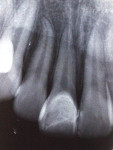

Follow-up after 7 years showed good adaptation of the tooth fragment/composite resin restoration, pulpal vitality, no signs of root resorption, and no painful symptomatology (Figure 7 and Figure 8).

After 7 years, the attached coronal fragment remained in position with good esthetics, and there were clinical and radiographic signs of pulpal vitality, periodontal health, and root integrity, thus indicating success. However, as with any trauma case, periodic evaluation is necessary in order to detect any evidence of pulpal necrosis and/or root resorption.